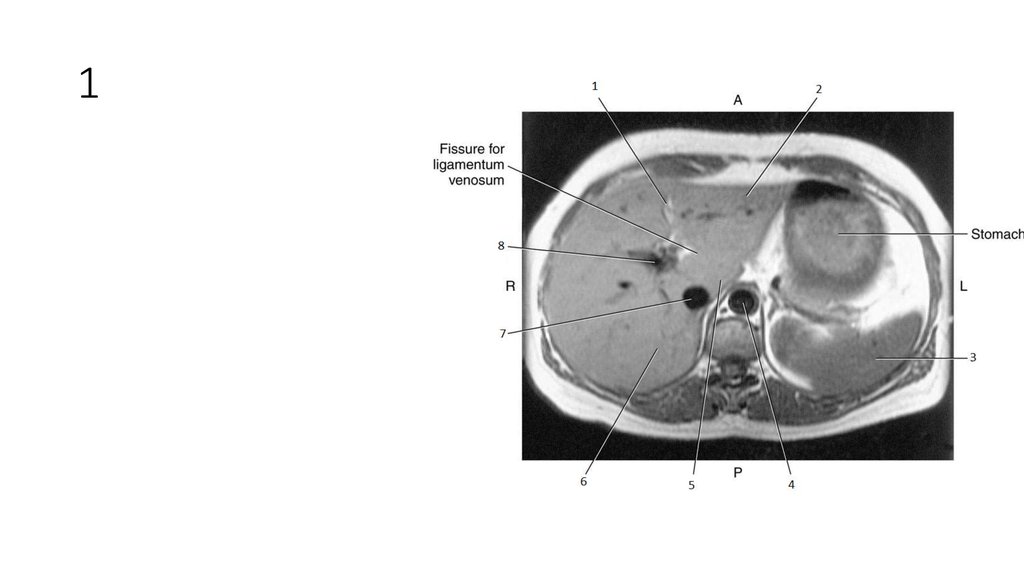

1

2

3

4

5

6

7

8